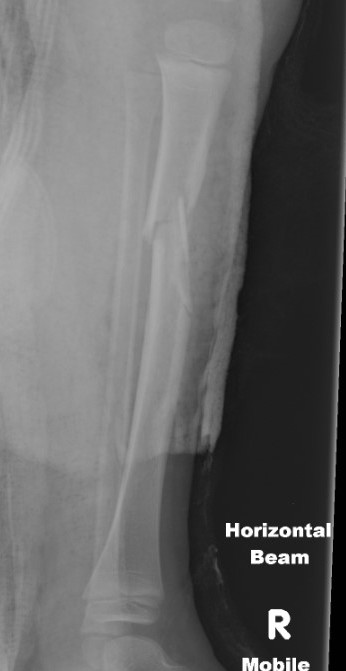

Technique

GA / II

- leg hanging over edge of bed

- gravity assists reduction

- apply short leg cast

- check II

Apply long leg cast in 45° knee flexion